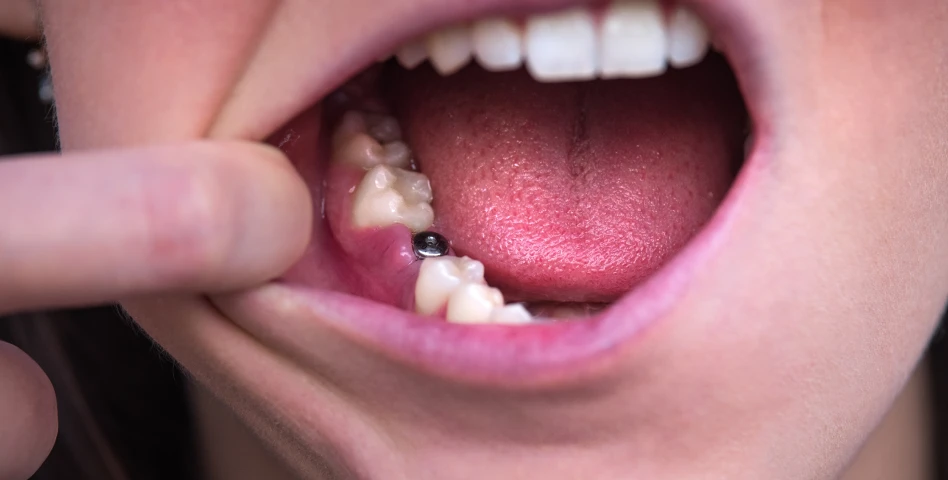

C’est une racine artificielle en titane placée dans l’os de la mâchoire pour remplacer une dent manquante.